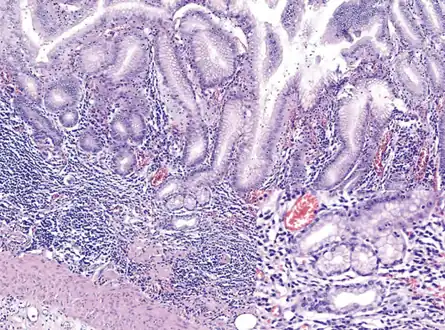

Histopathology of antral mucosa with atrophy. H&E 10x. Antral gastric mucosa with accentuated atrophy because replacement by extensive intestinal metaplasia.

Histopathology of fundic mucosa with atrophy. H&E 10x; square 20x. Fundic-corporal gastric mucosa with extensive loss of gastric glands, partially replaced by pseudo-pyloric metaplasia.